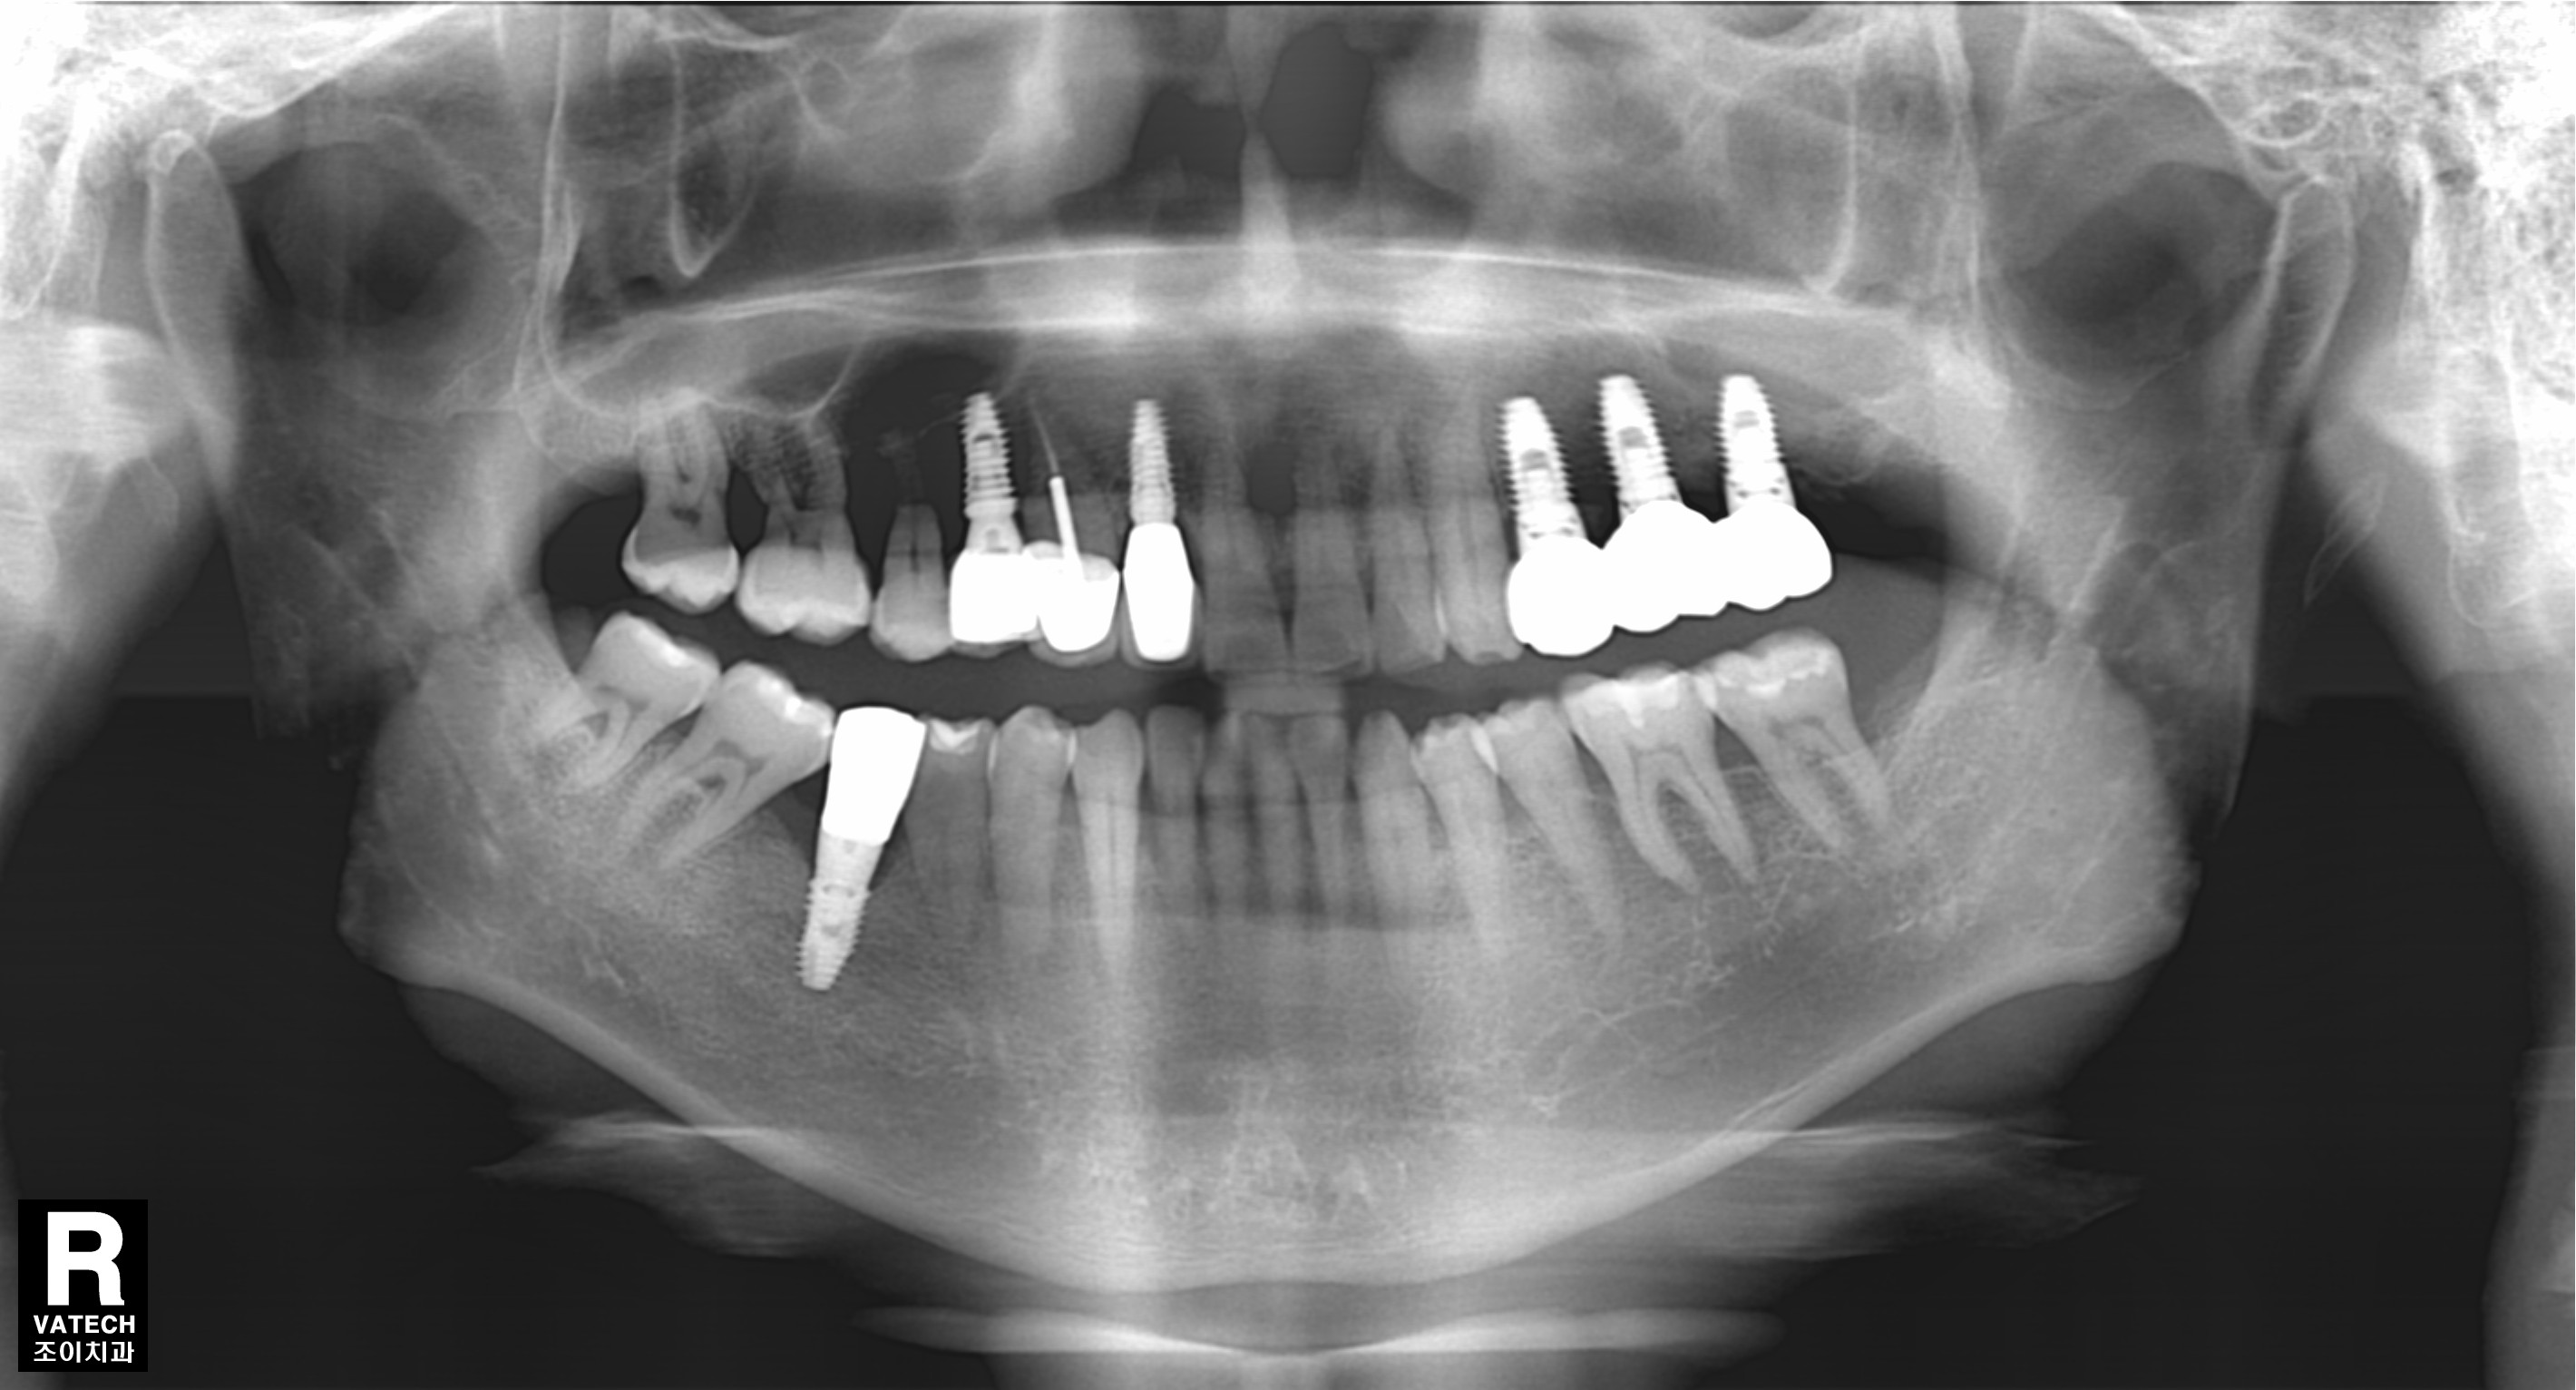

[임플란트] 제목 : 골이식

올바른 임플란트 식립의 초석은 충분한 뼈.